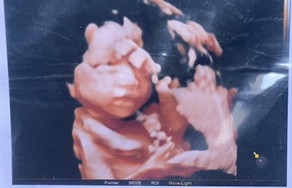

พาสาวน้อยมาแจกรอยยิ้มค่ะ 29w5dแล้ว❤️

Post reply image